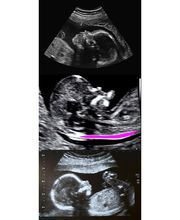

Il dr. Del Bianco Antongiulio è medico chirurgo specialista in ostetricia e ginecologia ed ha conseguito il dottorato di ricerca in fisiopatologia della riproduzione umana. Esegue, presso il proprio studio, visite ostetriche e ginecologiche, ecografie ostetriche e ginecologiche, pap test, tamponi vaginali ed esame a fresco cervico-vaginale. È accreditato presso la SIEOG (Società Italiana di Ecografia Ostetrico-Ginecologica) presso la Fetal Medicine Foundation di Londra (che ha frequentato per lungo tempo) in ambito ecografia in ostetricia e ginecologia ed in particolare per l'ecografia della translucenza nucale e per l'ecografia morfologica. Ha conseguito il master in ecocardiografia fetale nonché numerosi titoli in ambito delle indagini sul cuore fetale ed ecocardiografia fetale. Ha acquisito, inoltre, grandi esperienze nel campo della diagnostica prenatale invasiva (amniocentesi e villocentesi).